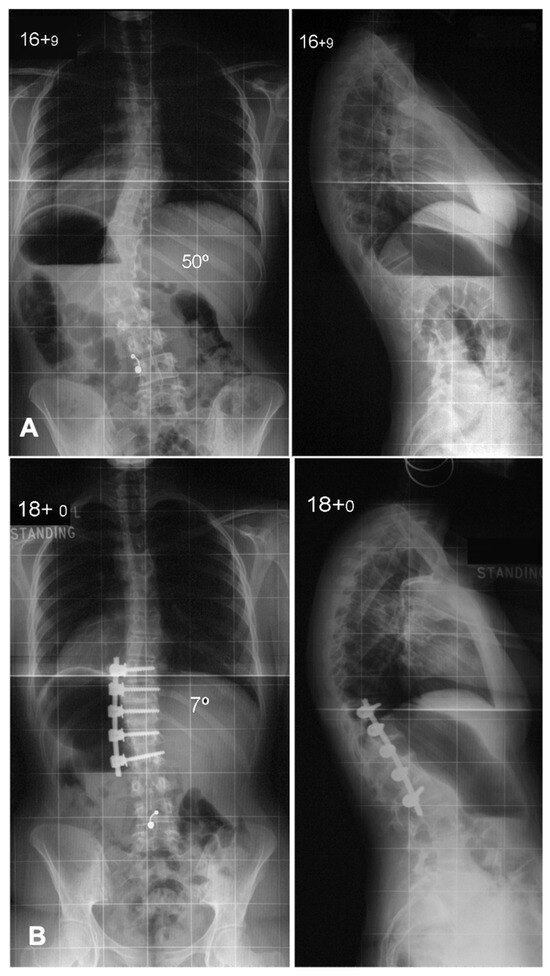

The global rod derotation technique, originally introduced by Cotrel and Dubousset, is based on the concept that the coronal deformity typical in AIS approximates the desired sagittal alignment when rotated 90° [51]. This method involves inserting a rod pre-contoured to the ideal sagittal shape on the curve’s concavity. The anchors are loosely attached to the rod and then rotated 90° along the axial plane to transform the coronal deformity into sagittal alignment [52,53]. The traditional use of the concave side for scoliosis correction poses challenges due to anatomical constraints. Studies, including that by Liljenqvist et al., reveal significantly narrower pedicles on the concave side at the thoracic curve apex, increasing the risk of cortical wall penetration [54]. Anekstein et al. evaluated the use of a convex rod derotation technique for correcting AIS in 40 patients treated with all-pedicle screw constructs and followed for two years. The mean preoperative Cobb angle of 60° improved to 17° postoperatively, with a 7% correction loss at follow-up, yielding a 71% major curve correction. The technique showed comparable outcomes to traditional concave-side corrections, with additional benefits of reduced neurological risks due to safer screw placement on the convex side. Thoracic kyphosis decreased slightly, and no major complications, infections, or revisions were reported [55]. This approach benefits from the stability offered by multiple fixation points, distributing mechanical stress and reducing localized anchor strain. It is particularly effective for thoracic hypokyphosis, enabling simultaneous correction in both the coronal and sagittal planes. However, this technique does not correct axial plane deformities. Advanced imaging has shown that while previously thought to induce rotational correction at the apex, it primarily results in translational adjustment. Additionally, the ideal sagittal contour may not align with the coronal deformity, potentially leading to suboptimal sagittal apex placement post-rotation [46,56]. A case example is shown in Figure 2.